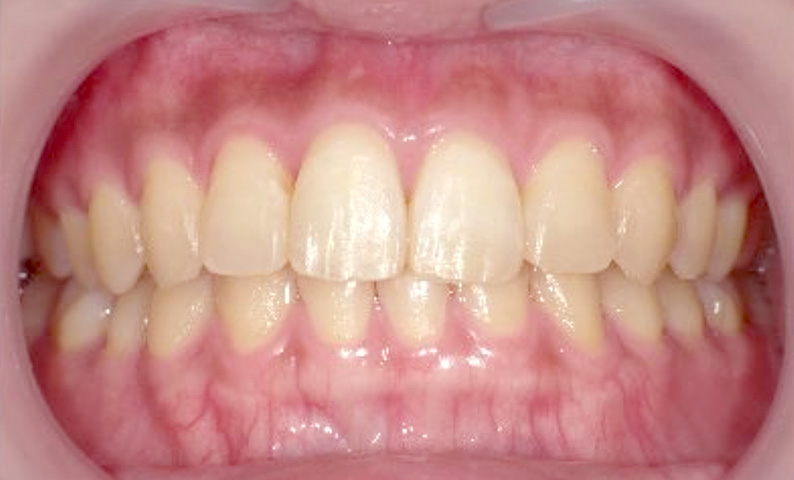

症例_025 上下顎の部分矯正

治療期間:13ヶ月金額:51万円+税女性前歯のガタガタ出っ歯

| Before | After |

|---|---|

|